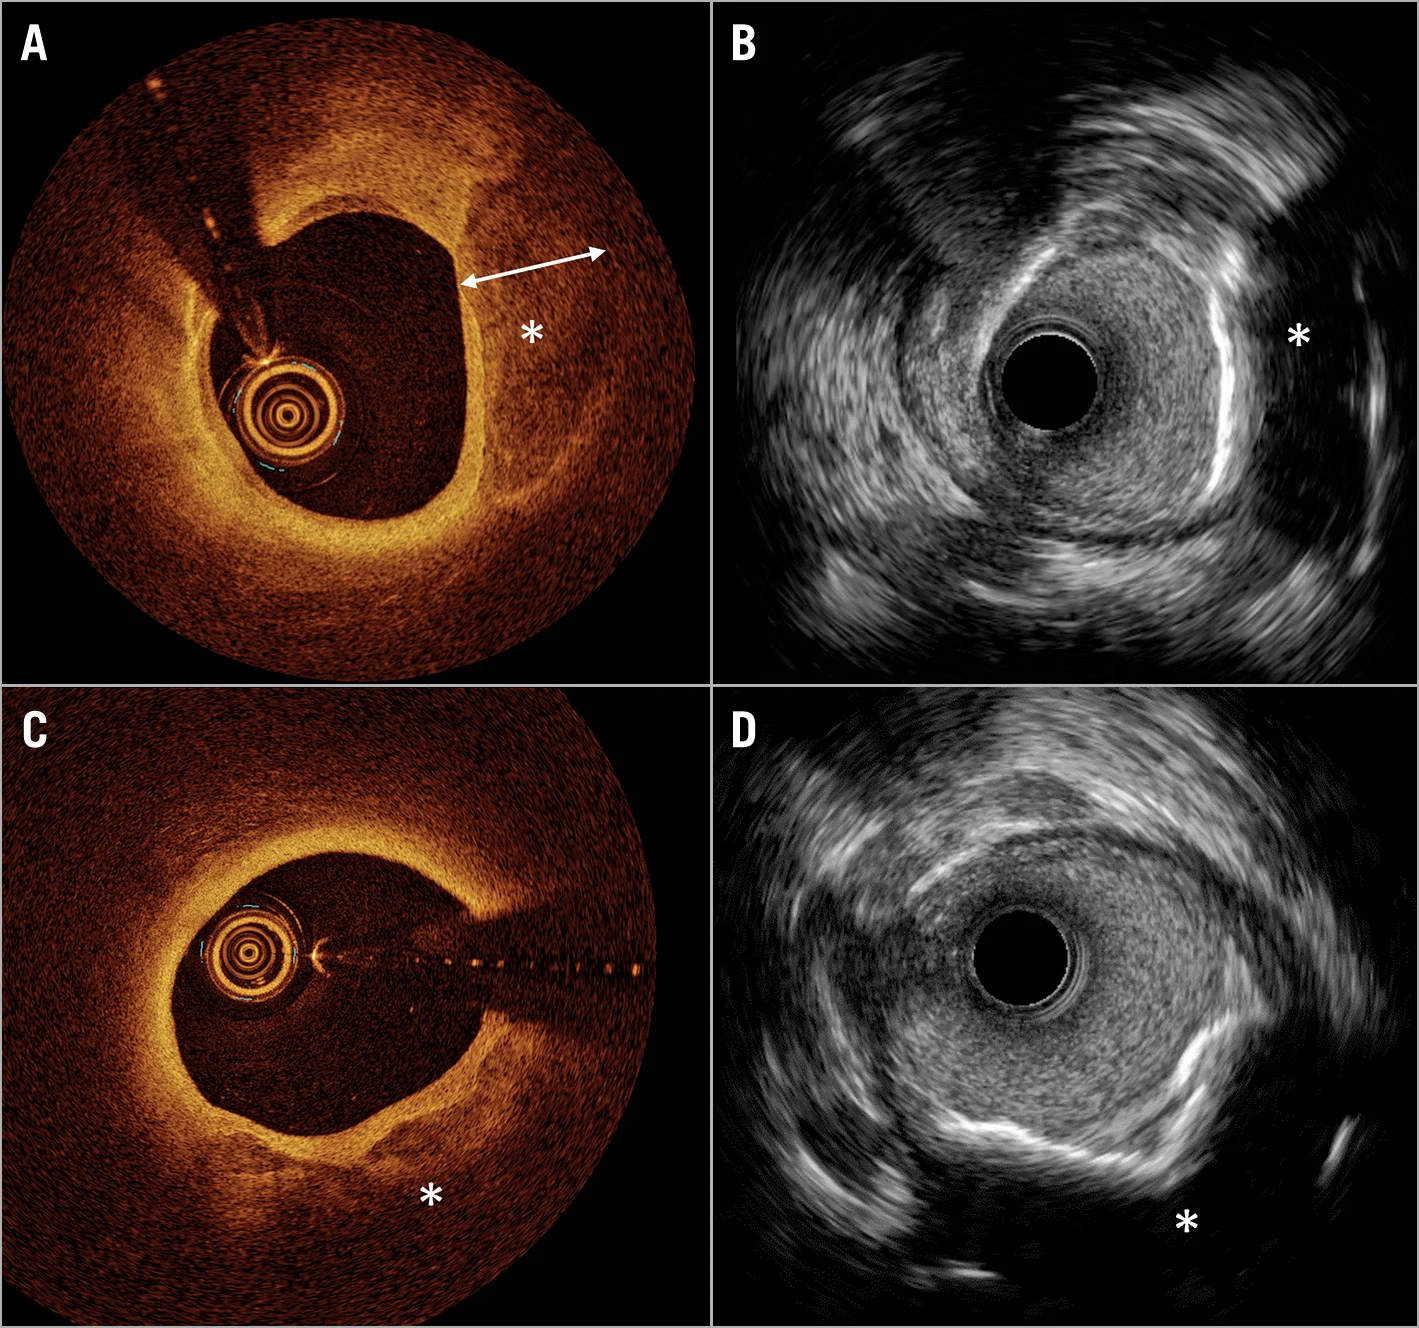

Our cardiac imaging suite includes Optical Coherence Tomography technology treatment to guide precise interventional decisions and optimise outcomes.

Our Department of Cardiology at SP Medifort provides a full range of innovative, minimally invasive cardiac procedures. Our team includes top cardiology specialists in Kerala, backed by a multidisciplinary unit for diagnosis and treatment of cardiac conditions. We offer advanced interventional therapies including Optical Coherence Tomography technology treatment, Atherectomy, Percutaneous Transluminal Coronary Angioplasty (PTCA), and Transcatheter Aortic Valve Implantation (TAVI) as part of comprehensive cardiac care. We guarantee safe, accurate, and prompt treatment for all heart-related diseases using modern technology, skilled interventional experienced cardiologists, and 24-hour emergency Cardiac Patient care.

Modern imaging technologies are used by SP Medifort to precisely guide complicated angioplasty situations.